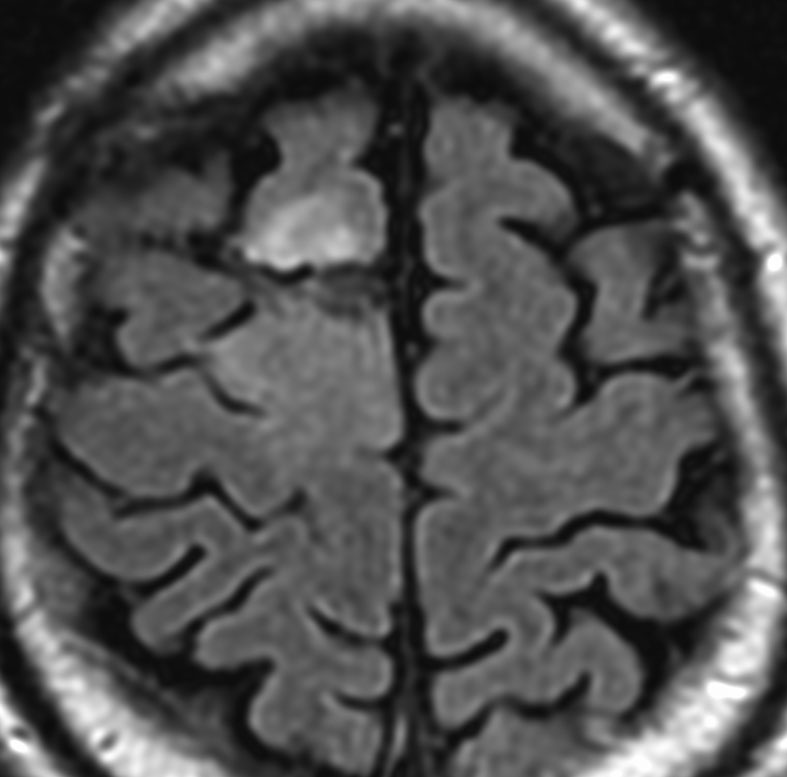

認知症で発症した60代男性の乏突起膠腫です。巨大で周囲の脳を圧迫する腫瘍でしたから,手術で部分摘出した後に放射線も化学療法も何もしないで経過観察しましたが,患者さんは社会復帰して仕事に戻れました。その後,無治療で13年が経過した時のMRIです。この13年間にほとんど大きくなっていません。このように高分化型とされる乏突起膠腫には,何もしないで様子を見ても長期間にわたって増大しない良性のものもあります。